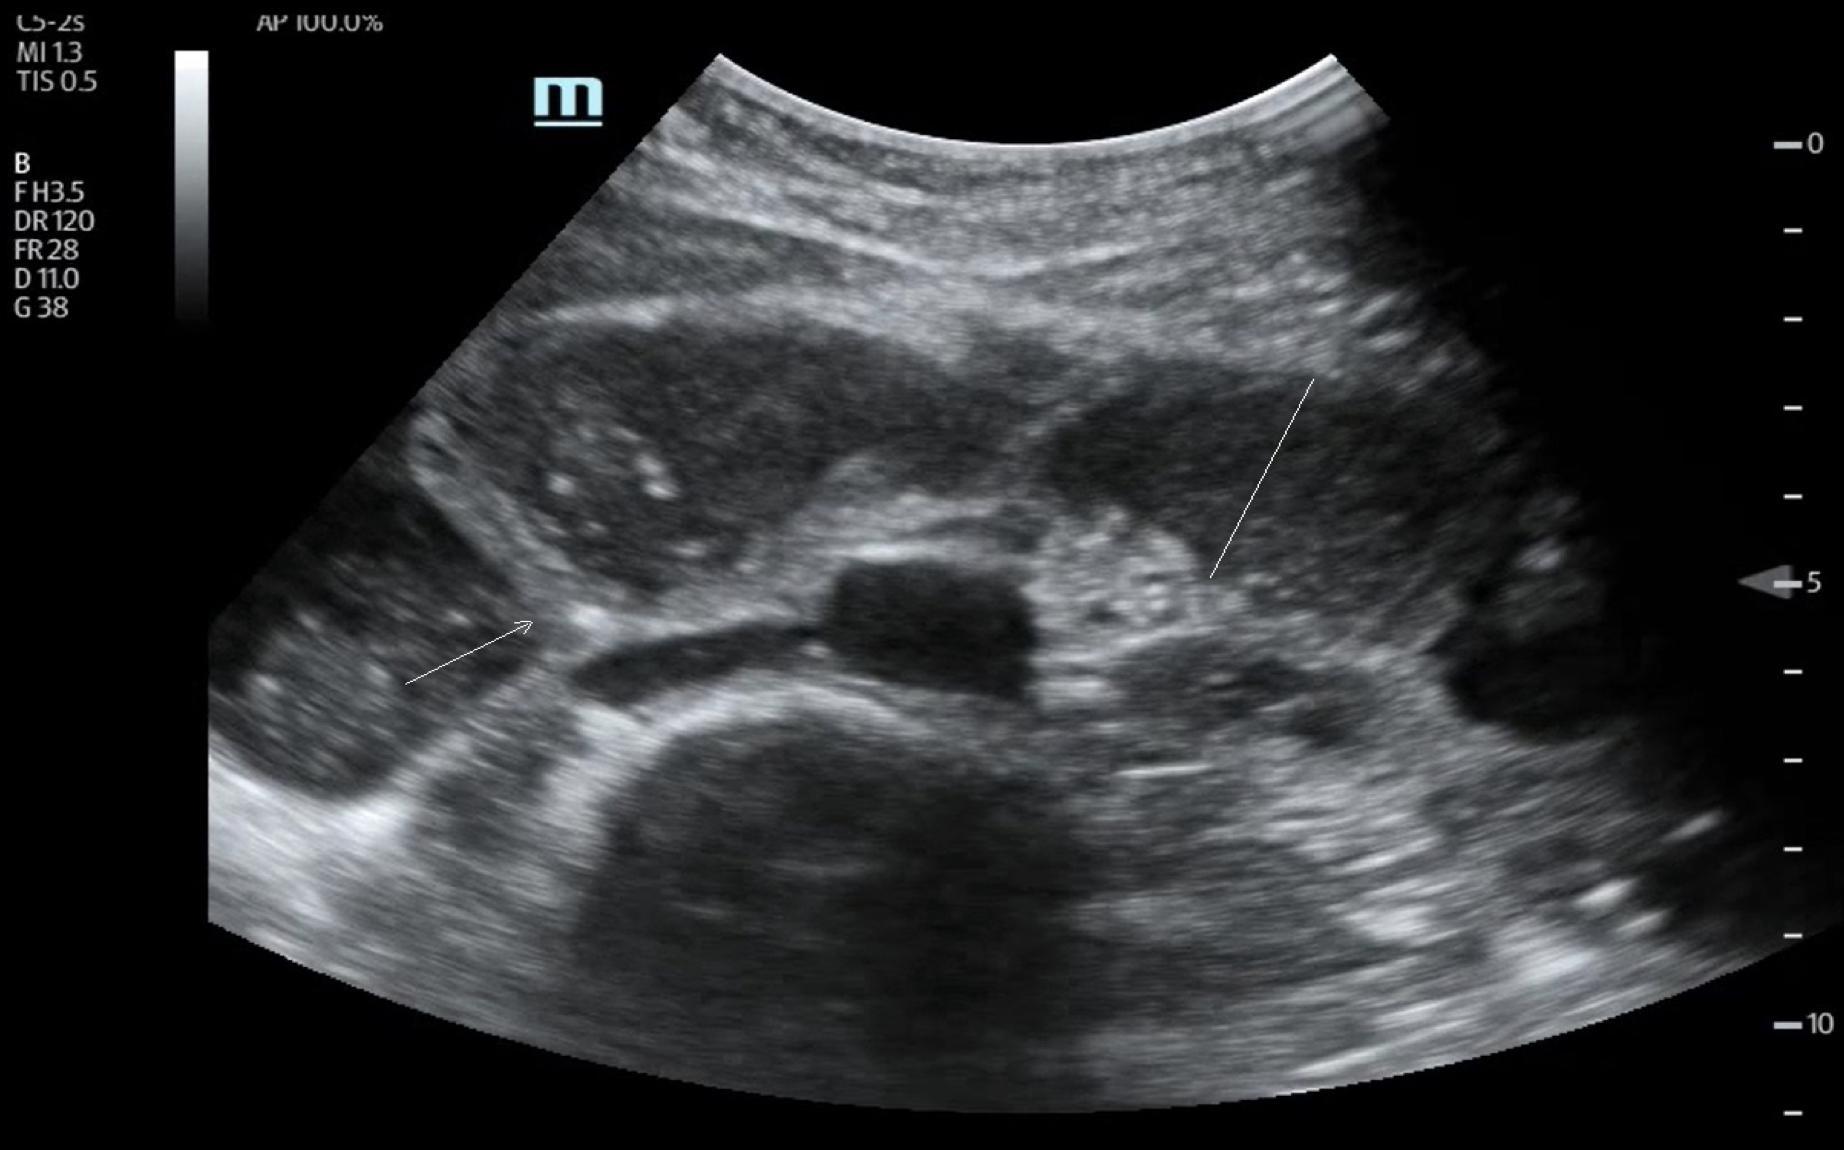

- Dilatation des anses grêles : diamètre > 25 mm (> 2,5 cm), contenu liquidien, paroi fine.

- Signe du tourbillon : mouvement de va-et-vient du contenu intestinal.

💧 Rechercher un épanchement inter-anse : marqueur de souffrance digestive.